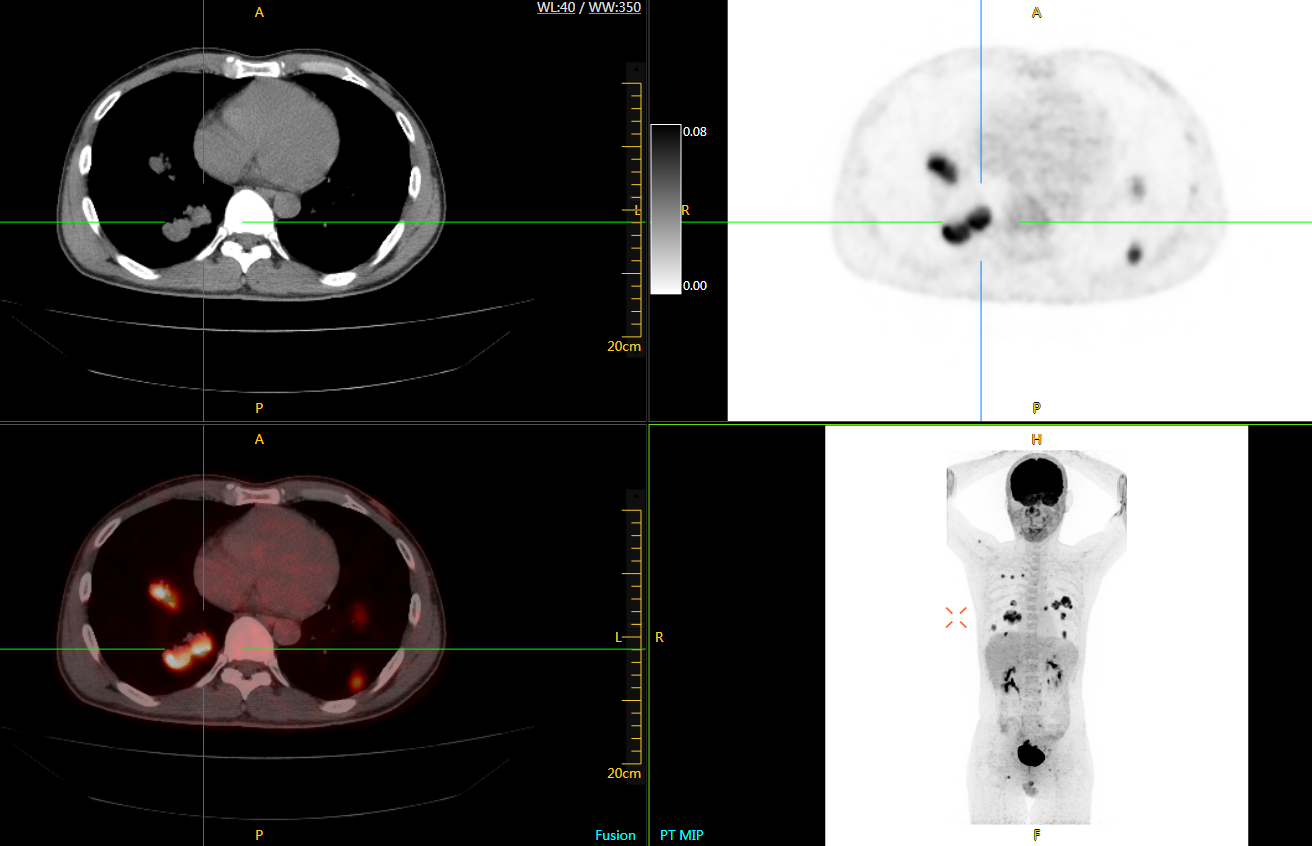

目前聯(lián)影在PET-CT領(lǐng)域的主要產(chǎn)品有:96環(huán)光導(dǎo)PET-CT和uExplorer探索者。其中,uExplorer探索者是由聯(lián)影與美國(guó)分子影像科研聯(lián)盟探索者共同研發(fā)的。uExplorer探索者是世界首臺(tái)全景掃描PET-CT,長(zhǎng)達(dá)2米,繼承了聯(lián)影PET家族的優(yōu)秀基因——具備業(yè)界最高2.8mm空間分辨率與先進(jìn)的飛行時(shí)間(Time of Flight,TOF)技術(shù)。

可4D呈現(xiàn)體內(nèi)藥物實(shí)時(shí)代謝情況,讓全身藥效可視化,全方位評(píng)估療效,加速藥物研發(fā);可精準(zhǔn)定位腫瘤位置,監(jiān)控腫瘤微轉(zhuǎn)移,助力定點(diǎn)靶向治療,讓腫瘤無(wú)處可藏;科研探索領(lǐng)域,以代謝信息判斷神經(jīng)膠質(zhì)細(xì)胞變化,讓細(xì)胞“開(kāi)口說(shuō)話(huà)”,助力多器官神經(jīng)關(guān)聯(lián)研究…

uExplorer探索者不再局限于傳統(tǒng)靜態(tài)代謝過(guò)程3D成像,而是在此基礎(chǔ)上新增一個(gè)維度——時(shí)間,從而實(shí)現(xiàn)4D全景成像。

注射總劑量為7.8mCi,14分鐘全身采集時(shí)間,在擁有超高靈敏度與超高分辨率的uEXPLORER上,即可得到展示顯示人體諸多精細(xì)結(jié)構(gòu)的高清三維圖像。

注射總劑量為7.8mCi,注射后1.6小時(shí),基于uEXPLORER探索者掃描1分鐘的圖像

注射總劑量為0.67 mCi FDG(低于常規(guī)劑量的十分之一),基于uEXPLORER探索者掃描15分鐘的圖像

注射總劑量為6.9mCi,注射后10小時(shí),基于uEXPLORER探索者掃描14分鐘的圖像